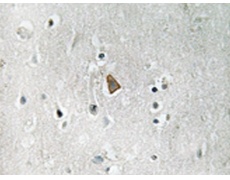

IHC positive control: |

Human brain tissue |